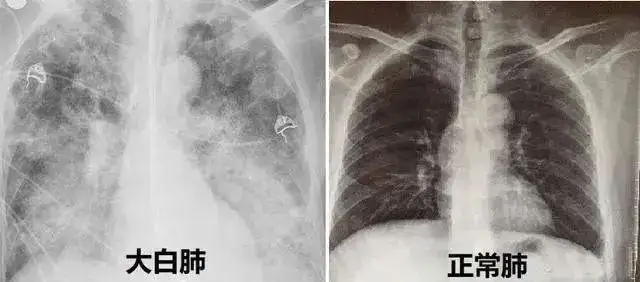

东南大学附属中大医院呼吸与危重症医学科主任章锐锋介绍,白肺不是一种具体的疾病,而是疾病的一种影像学表现。我们的肺是由肺泡组成的,正常情况下肺泡里充满了空气,进行CT或X线检查时,射线穿过肺泡,影像的表现应该是黑色的区域。

但当肺泡里边出现炎症和感染,有渗出液和炎性细胞时,肺泡就被这些渗出液或炎性细胞填充,肺脏中的气体含量减少,这样射线就穿不透,在影像学上的表现就是出现了白色区域,这个白色区域反映出来的是渗出物的影像学表现,并不是说肺脏的组织和实体变成了白色。

并不是只要肺部出现了炎症都叫白肺,比较严重的肺炎表现才会出现白肺。一般来讲,肺部的炎症比较重、渗出液较多时,即白色的影像区面积达到70%~80%时,才在临床上把它称为白肺。